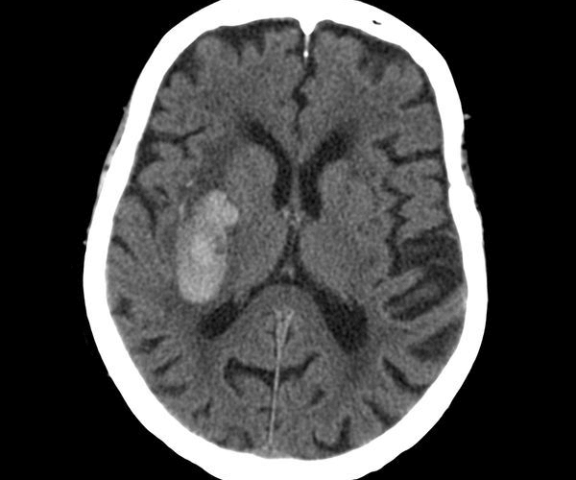

Показания для проведения данного вида КТ: заболевания головного мозга, мозговых оболочек, костей черепа, а также травматические поражения указанных структур. Первичные и вторичные объемные поражения головного мозга и вокруг мозговых структур.